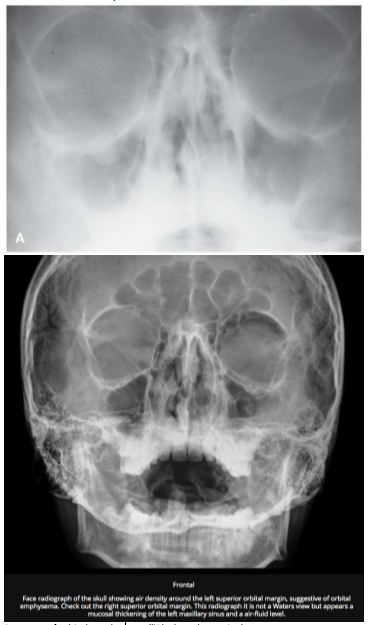

Fleisher’s Chapter 115 Facial Trauma

Up To Date Orbital Fractures

Radiopaedia Facial Fractures https://radiopaedia.org/articles/orbital-blowout-fracture-1